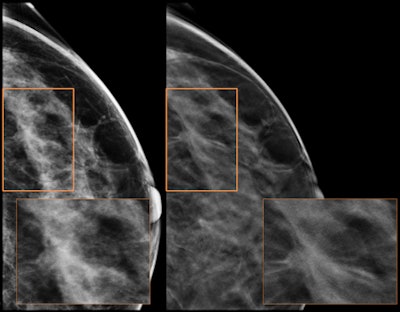

| Craniocaudal tomosynthesis views demonstrate spiculated mass not seen on 2D exam in the upper outer quadrant. Image courtesy of Dr. Stephen Rose, TOPS Comprehensive Breast Center. |